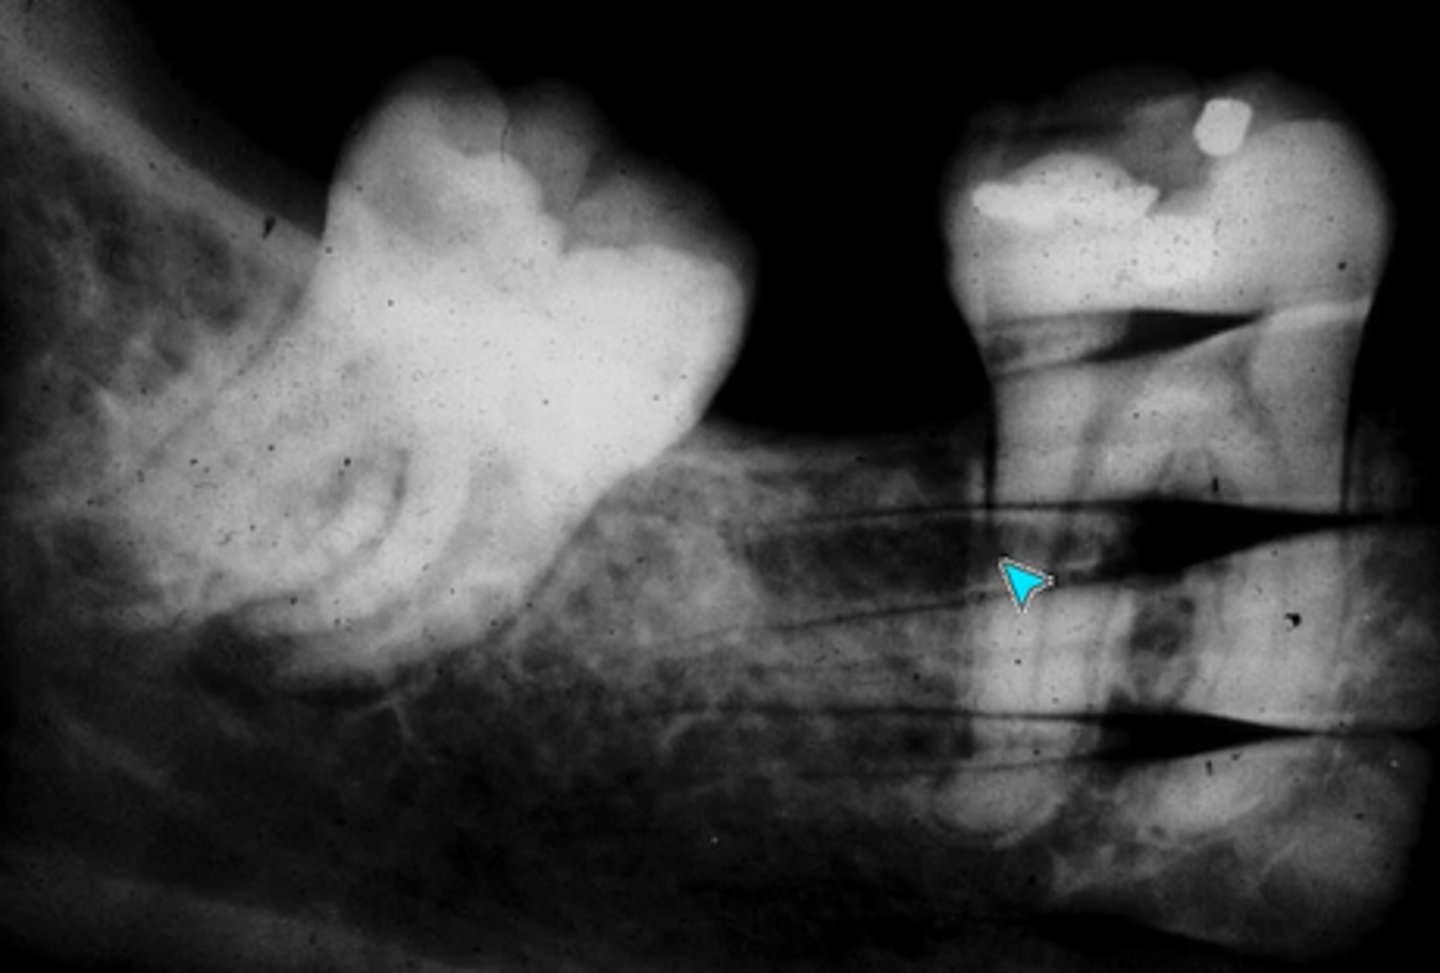

What error occurred here?

Developer time or temperature is too low